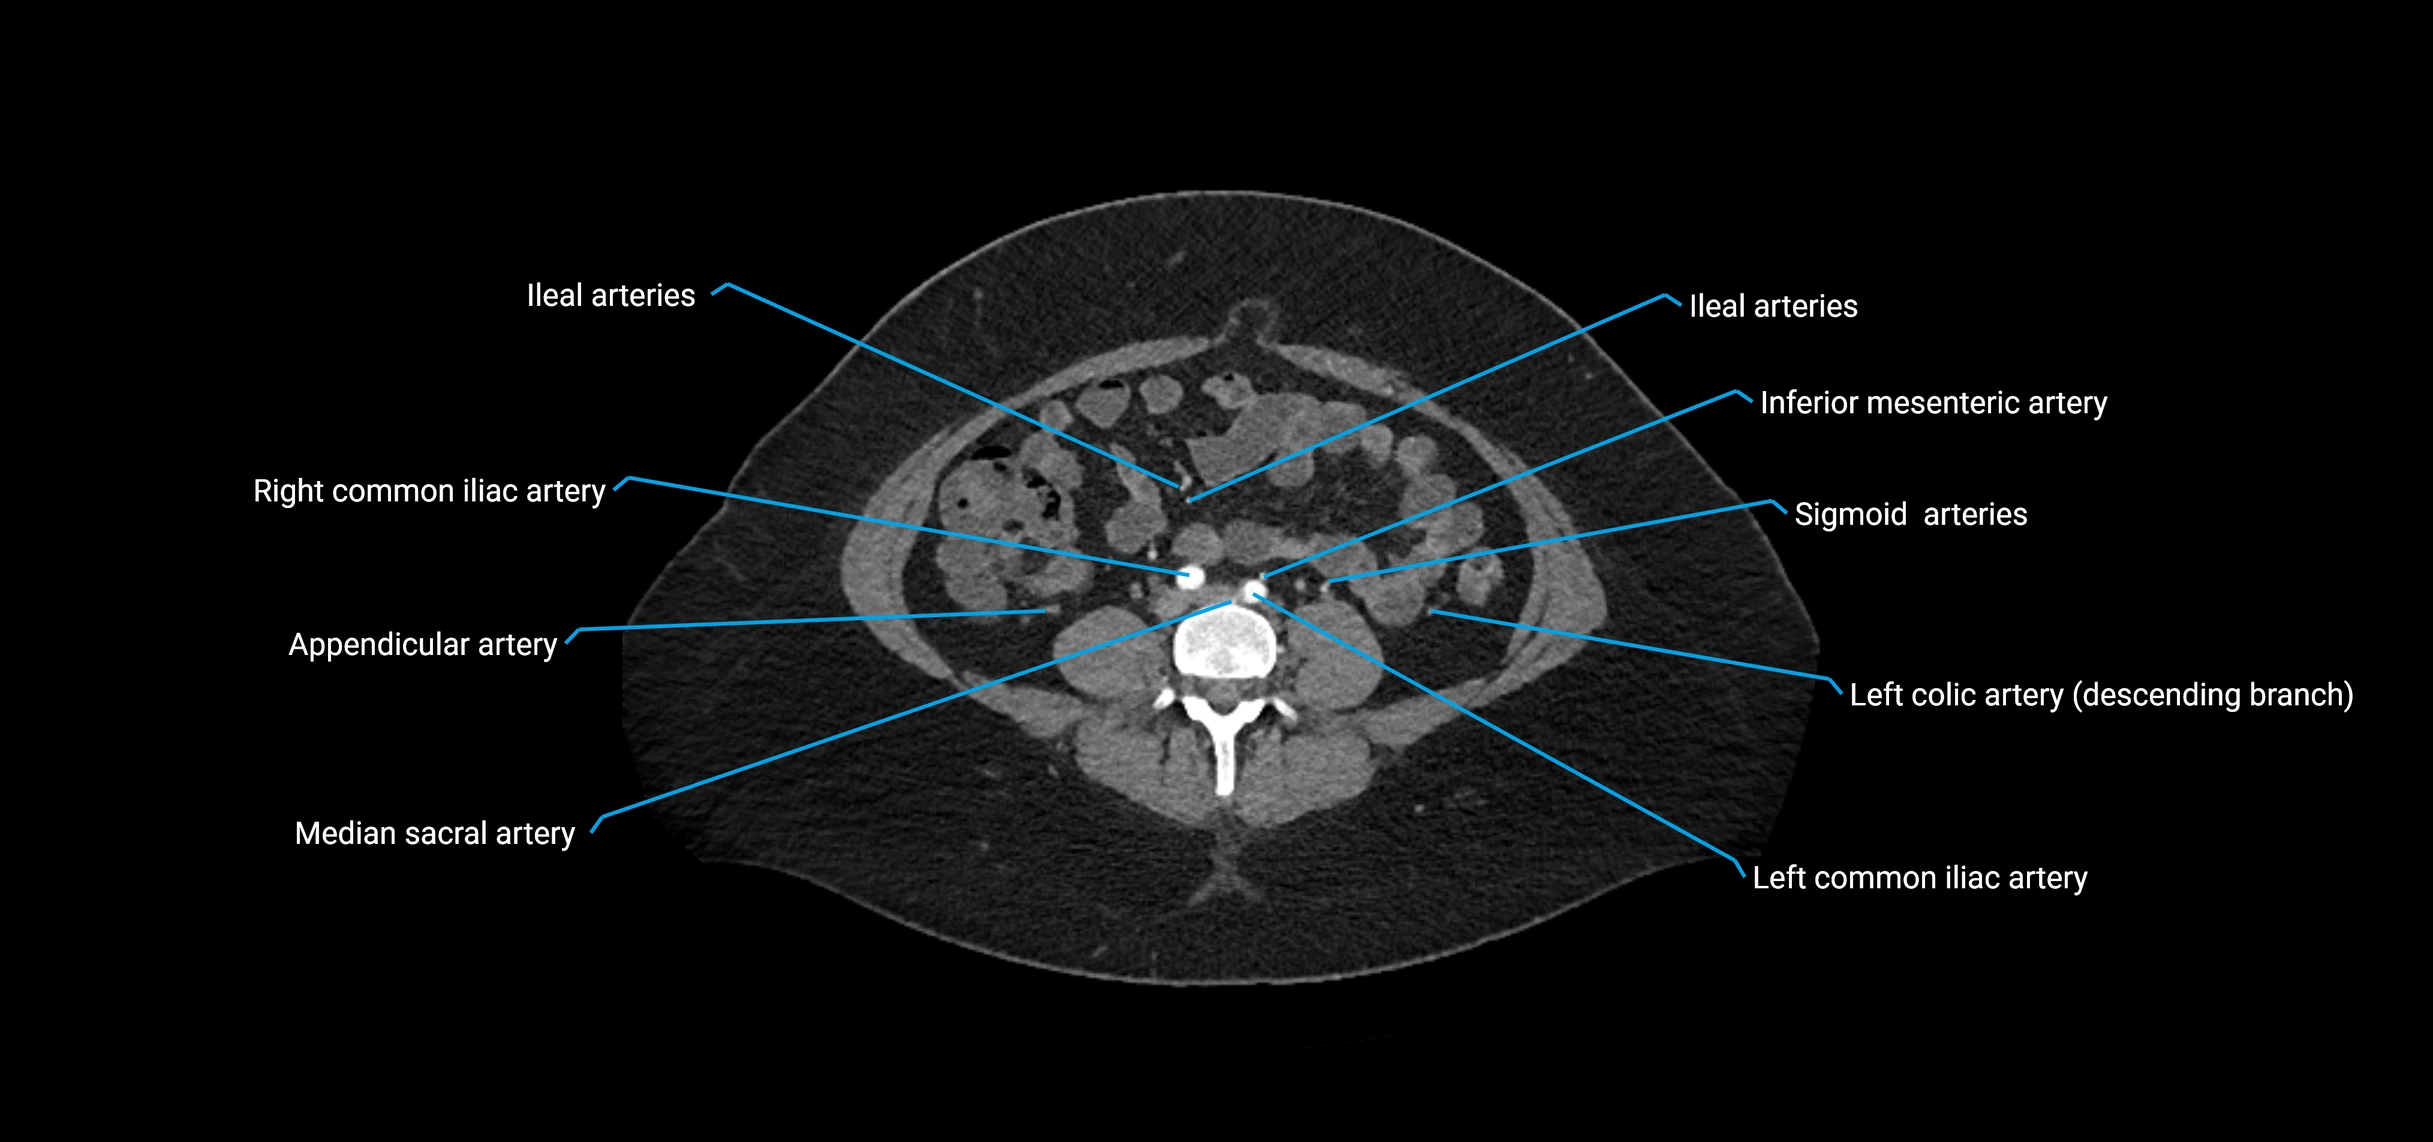

The abdominal aorta is the continuation of the thoracic aorta, beginning at the level of the aortic hiatus of the diaphragm (T12 vertebra) and terminating at the level of the L4 vertebra where it bifurcates into the right and left common iliac arteries. It lies slightly to the left of the midline and courses anterior to the vertebral bodies, surrounded by the retroperitoneal structures of the abdomen.

Branches

• Unpaired visceral branches: celiac trunk, superior mesenteric artery (SMA), inferior mesenteric artery (IMA)

• Paired visceral branches: middle suprarenal arteries, renal arteries, gonadal arteries (testicular or ovarian)

• Parietal branches: inferior phrenic arteries, lumbar arteries, median sacral artery

• Terminal branches: right and left common iliac arteries

Contrast-enhanced CT (CTA):

• Gold standard for abdominal aortic imaging

• Provides excellent detail of lumen, wall, aneurysm, thrombus, and branch vessels

• Multiplanar and 3D reconstructions help in aneurysm measurement, stent graft planning, and dissection evaluation

• Detects acute rupture, traumatic injury, or occlusion with high sensitivity

CT images

image